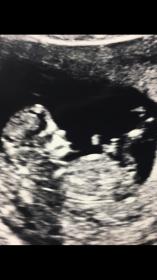

Here's My 12 week ultrasound pics! (11+6)

Would be so thankful if you guys could help me guess ❤️

Tentative girl lean based on the second pic. I can’t quite tell if the nub is on the rise, so I’m not overly confident of my guess.

A tad earlier than I'd like to guess. Sorry! Cute baby though. Congrats!